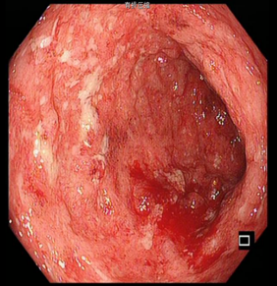

该患者入院时溃疡性结肠炎诊断明确,查血提示WBC16000/ml、HGB130g/L 、CRP29mg/L、ESR44mm/h、TP61g/L、ALB27g/L、pre-ALB120g/L。查ANA、ANCA、结核、EB、CMV(-)。肠镜提示患者全结肠粘膜连续性病变、弥漫性溃疡、粘膜充血水肿并覆白色脓液,结肠袋消失。CT提示全结肠弥漫性水肿、增厚,肠管僵硬。分析该患者溃疡性结肠反复发作、逐渐加重,并且应用美沙拉嗪、激素、免疫抑制剂及单抗治疗效果不佳,所以有全结肠切除的指征。但患者近3月内应用过类克及激素治疗,此时进行手术,势必会出现术后吻合口瘘、腹腔感染等严重并发症。

肠镜下肠粘膜表现    CT提示结肠肠管弥漫性病变   切除的结肠标本